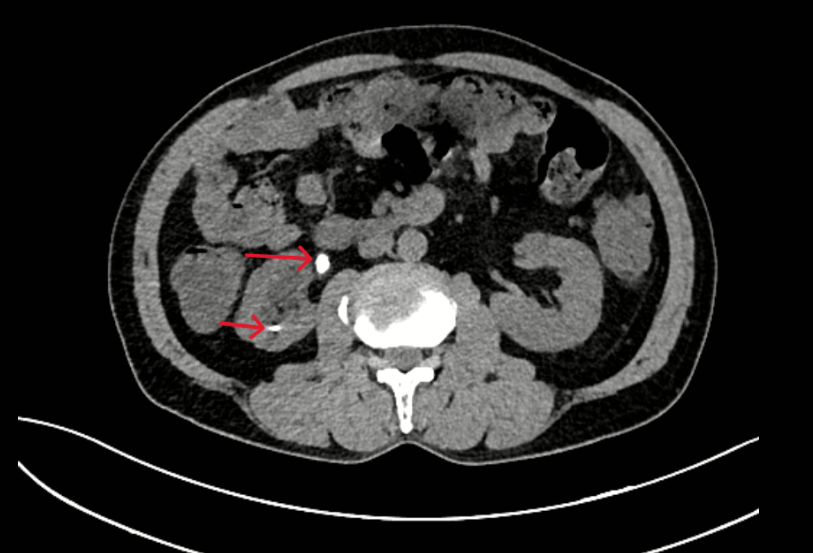

– Chụp CT bụng: Hình ảnh giãn đài bể thận và niệu quản phải do sỏi niệu quản đoạn 1/3 trên. Sỏi đài dưới thận phải.

Hình 2: Thận phải: Hình dạng và kích thước bình thường, nhu mô có nang 32mm. Đài bể thận giãn đường kính trước sau 15mm, đài dưới có sỏi kích thước 5mm. Niệu quản đoạn 1/3 trên giãn đường kính 9mm, có sỏi kích thước 7x13mm.

Hình 5: Hình ảnh đài – bể thận phải giãn độ II, còn sonde JJ niệu quản – bàng quang, nang thận phải đường kính 35 mm